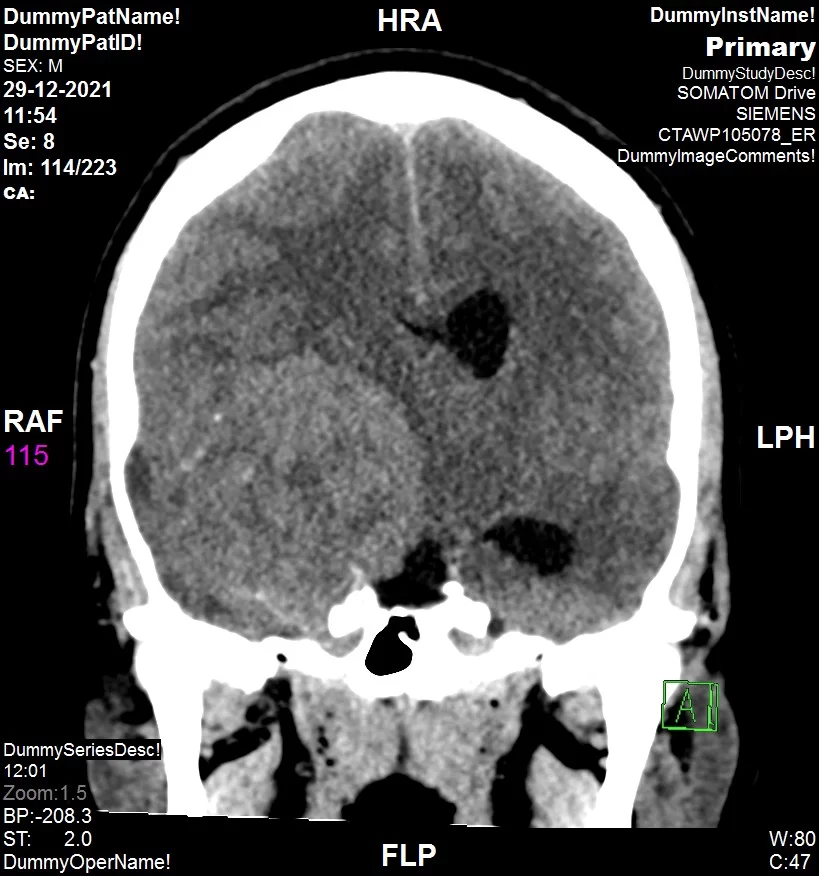

הצילום לא הותיר כל ספק, הצעיר סובל מגידול ענק מימדים בראשו וזה מה שיוצר את הלחץ הבלתי נסבל עד כדי איבוד הכרה "לרגעים אחדים היה נראה לנו שאנו מאבדים אותו חלילה ונערכנו לכל תרחיש שיתפתח", אומר ד"ר נבו מרגלית.

הצעיר הובהל אכן לניתוח דחוף במהלכו הוצא מראשו גידול ענק "בגודל של אשכולית" וכעבור מספר שעות בחדר התאוששות התעורר והחל לתקשר עם סובביו. הצוות הרפואי כמו גם בני המשפחה התרשמו מההתקדמות המהירה ואף מנכ"ל המרכז הרפואי שערי צדק פרופ' עופר מרין הגיע לבקר את הצעיר ולחזות בפלא.

הוריו של הצעיר סיפרו כי "מזה כמה שנים שהוא מתלונן על כאבי ראש ונאמר לנו שזה מגרנה. לפני כשנה וחצי בוצע לו סיטי ראש שיצא תקין ונקי לחלוטין ועל כן ההסבר היחיד היה מגרנה. מסתבר שבחודשים האחרונים בנוסף למיגרנה ממנה סבל, התפתח גידול בראש שהוסיף כאב ולחץ כבד ביותר".